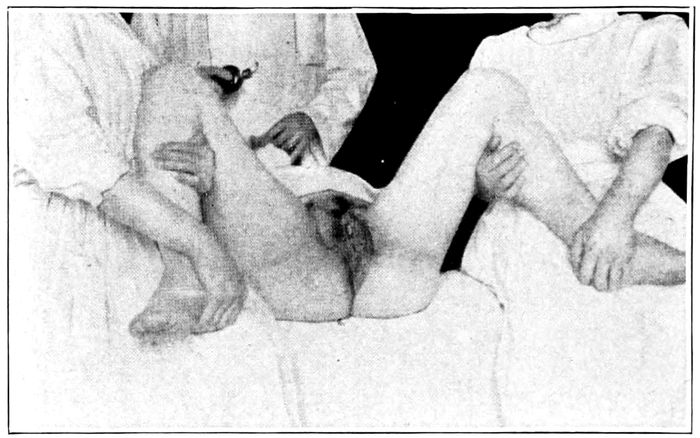

Forceps operation. Introduction of the left blade |

186 |

| |

| 75. |

Forceps operation. The introduction of the right blade |

187 |

| |

| 76. |

Forceps operation. Locking the handles |

187 |

| |

| 77. |

Forceps operation. The way the blades should grasp the fœtal head |

188 |

| |

| 78. |

Forceps operation. Traction on the handles |

189 |

| |

| 79. |

Forceps operation. The delivery of the head |

189 |